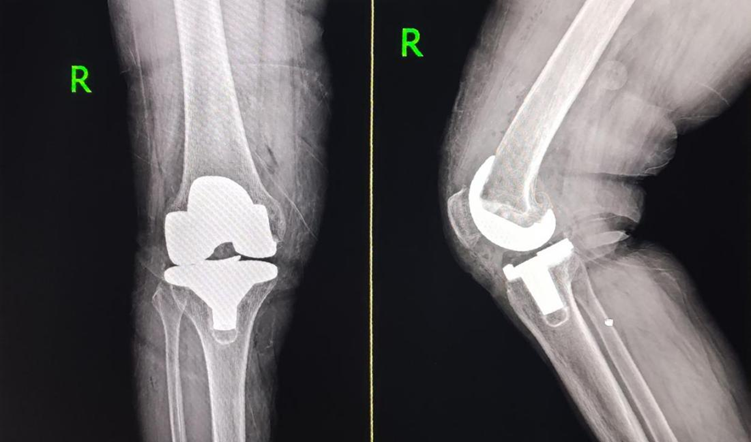

右膝术后

2025年12月、2026年4月,在医院手术团队的精心操作下,张阿姨先后成功接受了右膝、左膝关节置换手术。术后,医院依托先进的快速康复理念和责任制整体护理模式,为张阿姨制定了专属康复计划,医护人员每天定时查房、指导康复训练、关注身体恢复情况。